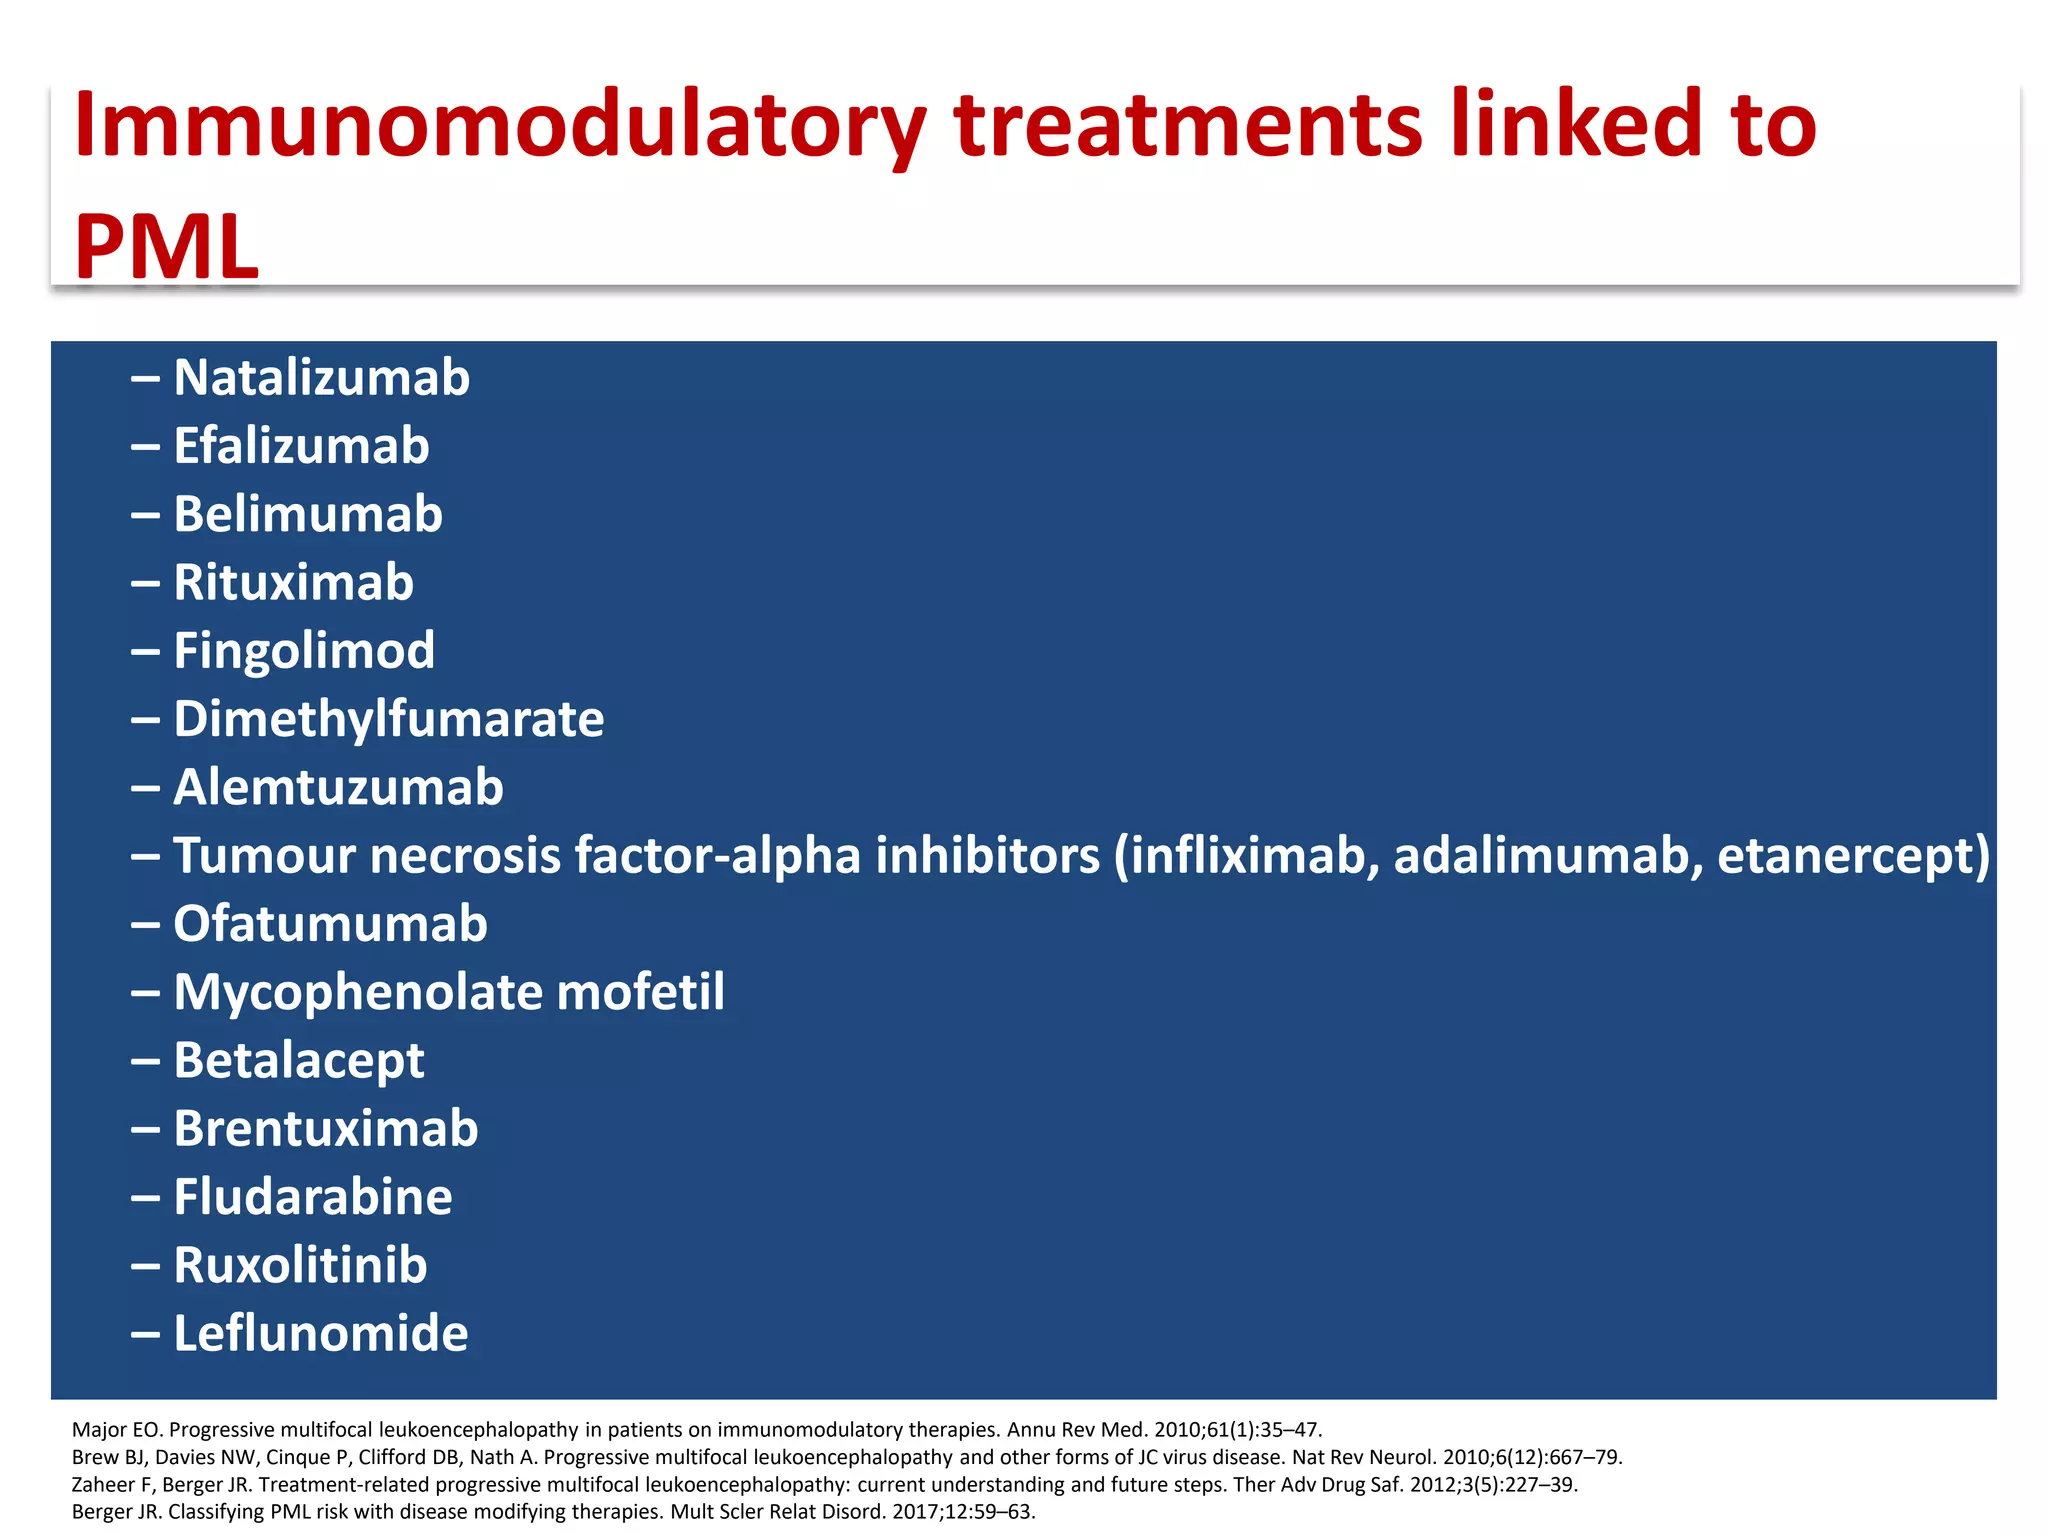

This document discusses progressive multifocal leukoencephalopathy (PML), an opportunistic infection caused by the John Cunningham virus (JCV) that leads to demyelination in the central nervous system. It highlights the epidemiology, clinical manifestations, diagnostic methods, and risk factors associated with PML, particularly in immunocompromised patients and those undergoing immunomodulatory therapies. It also presents data on the incidence of PML in patients treated with natalizumab and other therapies, addressing the relationships between these treatments and the development of PML.